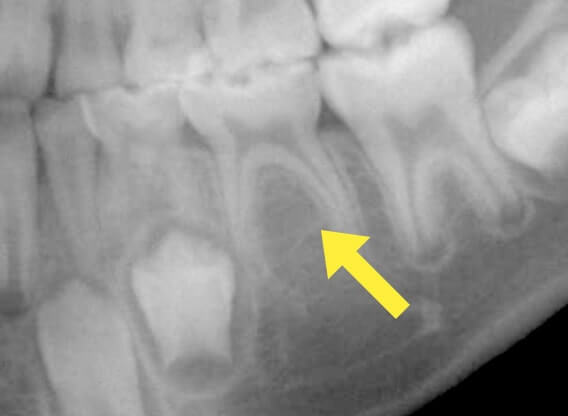

萌出異常(永久歯が乳歯に引っかかっている)